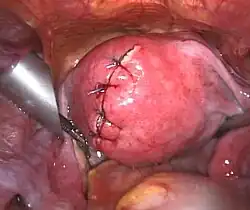

Befund nach Myomenentfernung per Bauchspiegelung

Befund nach Myomenentfernung per Bauchspiegelung